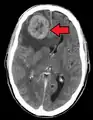

Illustration showing hematogenous metastasis